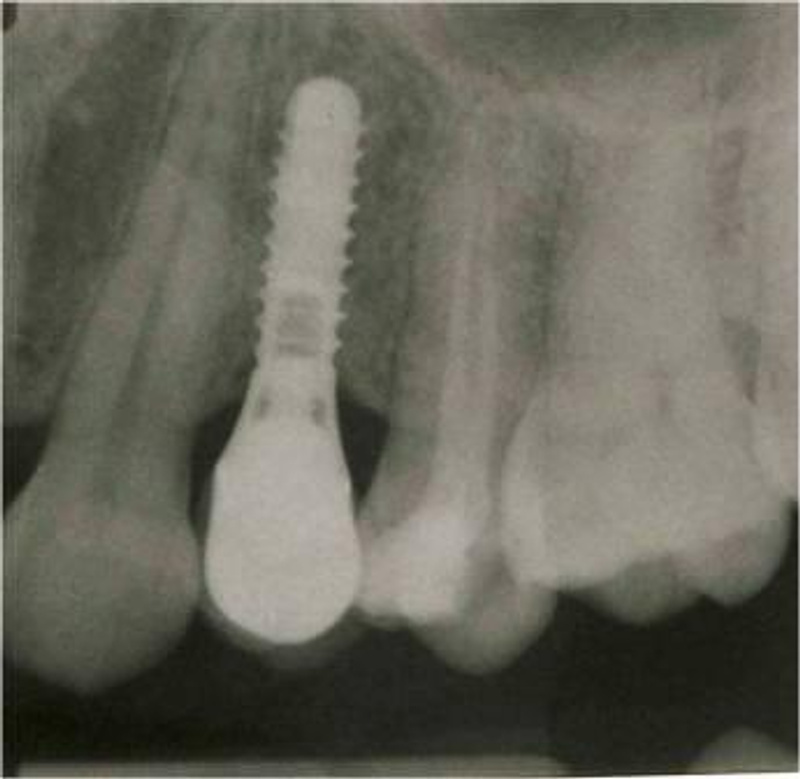

Вообще по идеи лучше всего конечно же ставить импланты ипортные!Ну и какие из этих надежнее или эстетичнее???![]()

Они намного надёжнее и эстетичнеее смотрятся, по сравнению с российскими имплантами!

Что лучше смотрится???Коли доктор сыт, так и больному легче

Вы сами посудите, или через несколько лет будут чёрные проявления от мет.кер, или в течении многих лет, ровные белоснежные коронки, согласитесь есть разница и между раскуроченой десной и аккуратно высверленной для импланта!![]()

а рядом зарубежные показаны, вот наподобие что вы картинку мне показали и как выглядят уже готовая работа, поэтому я вот так и написала, эт не правильно???